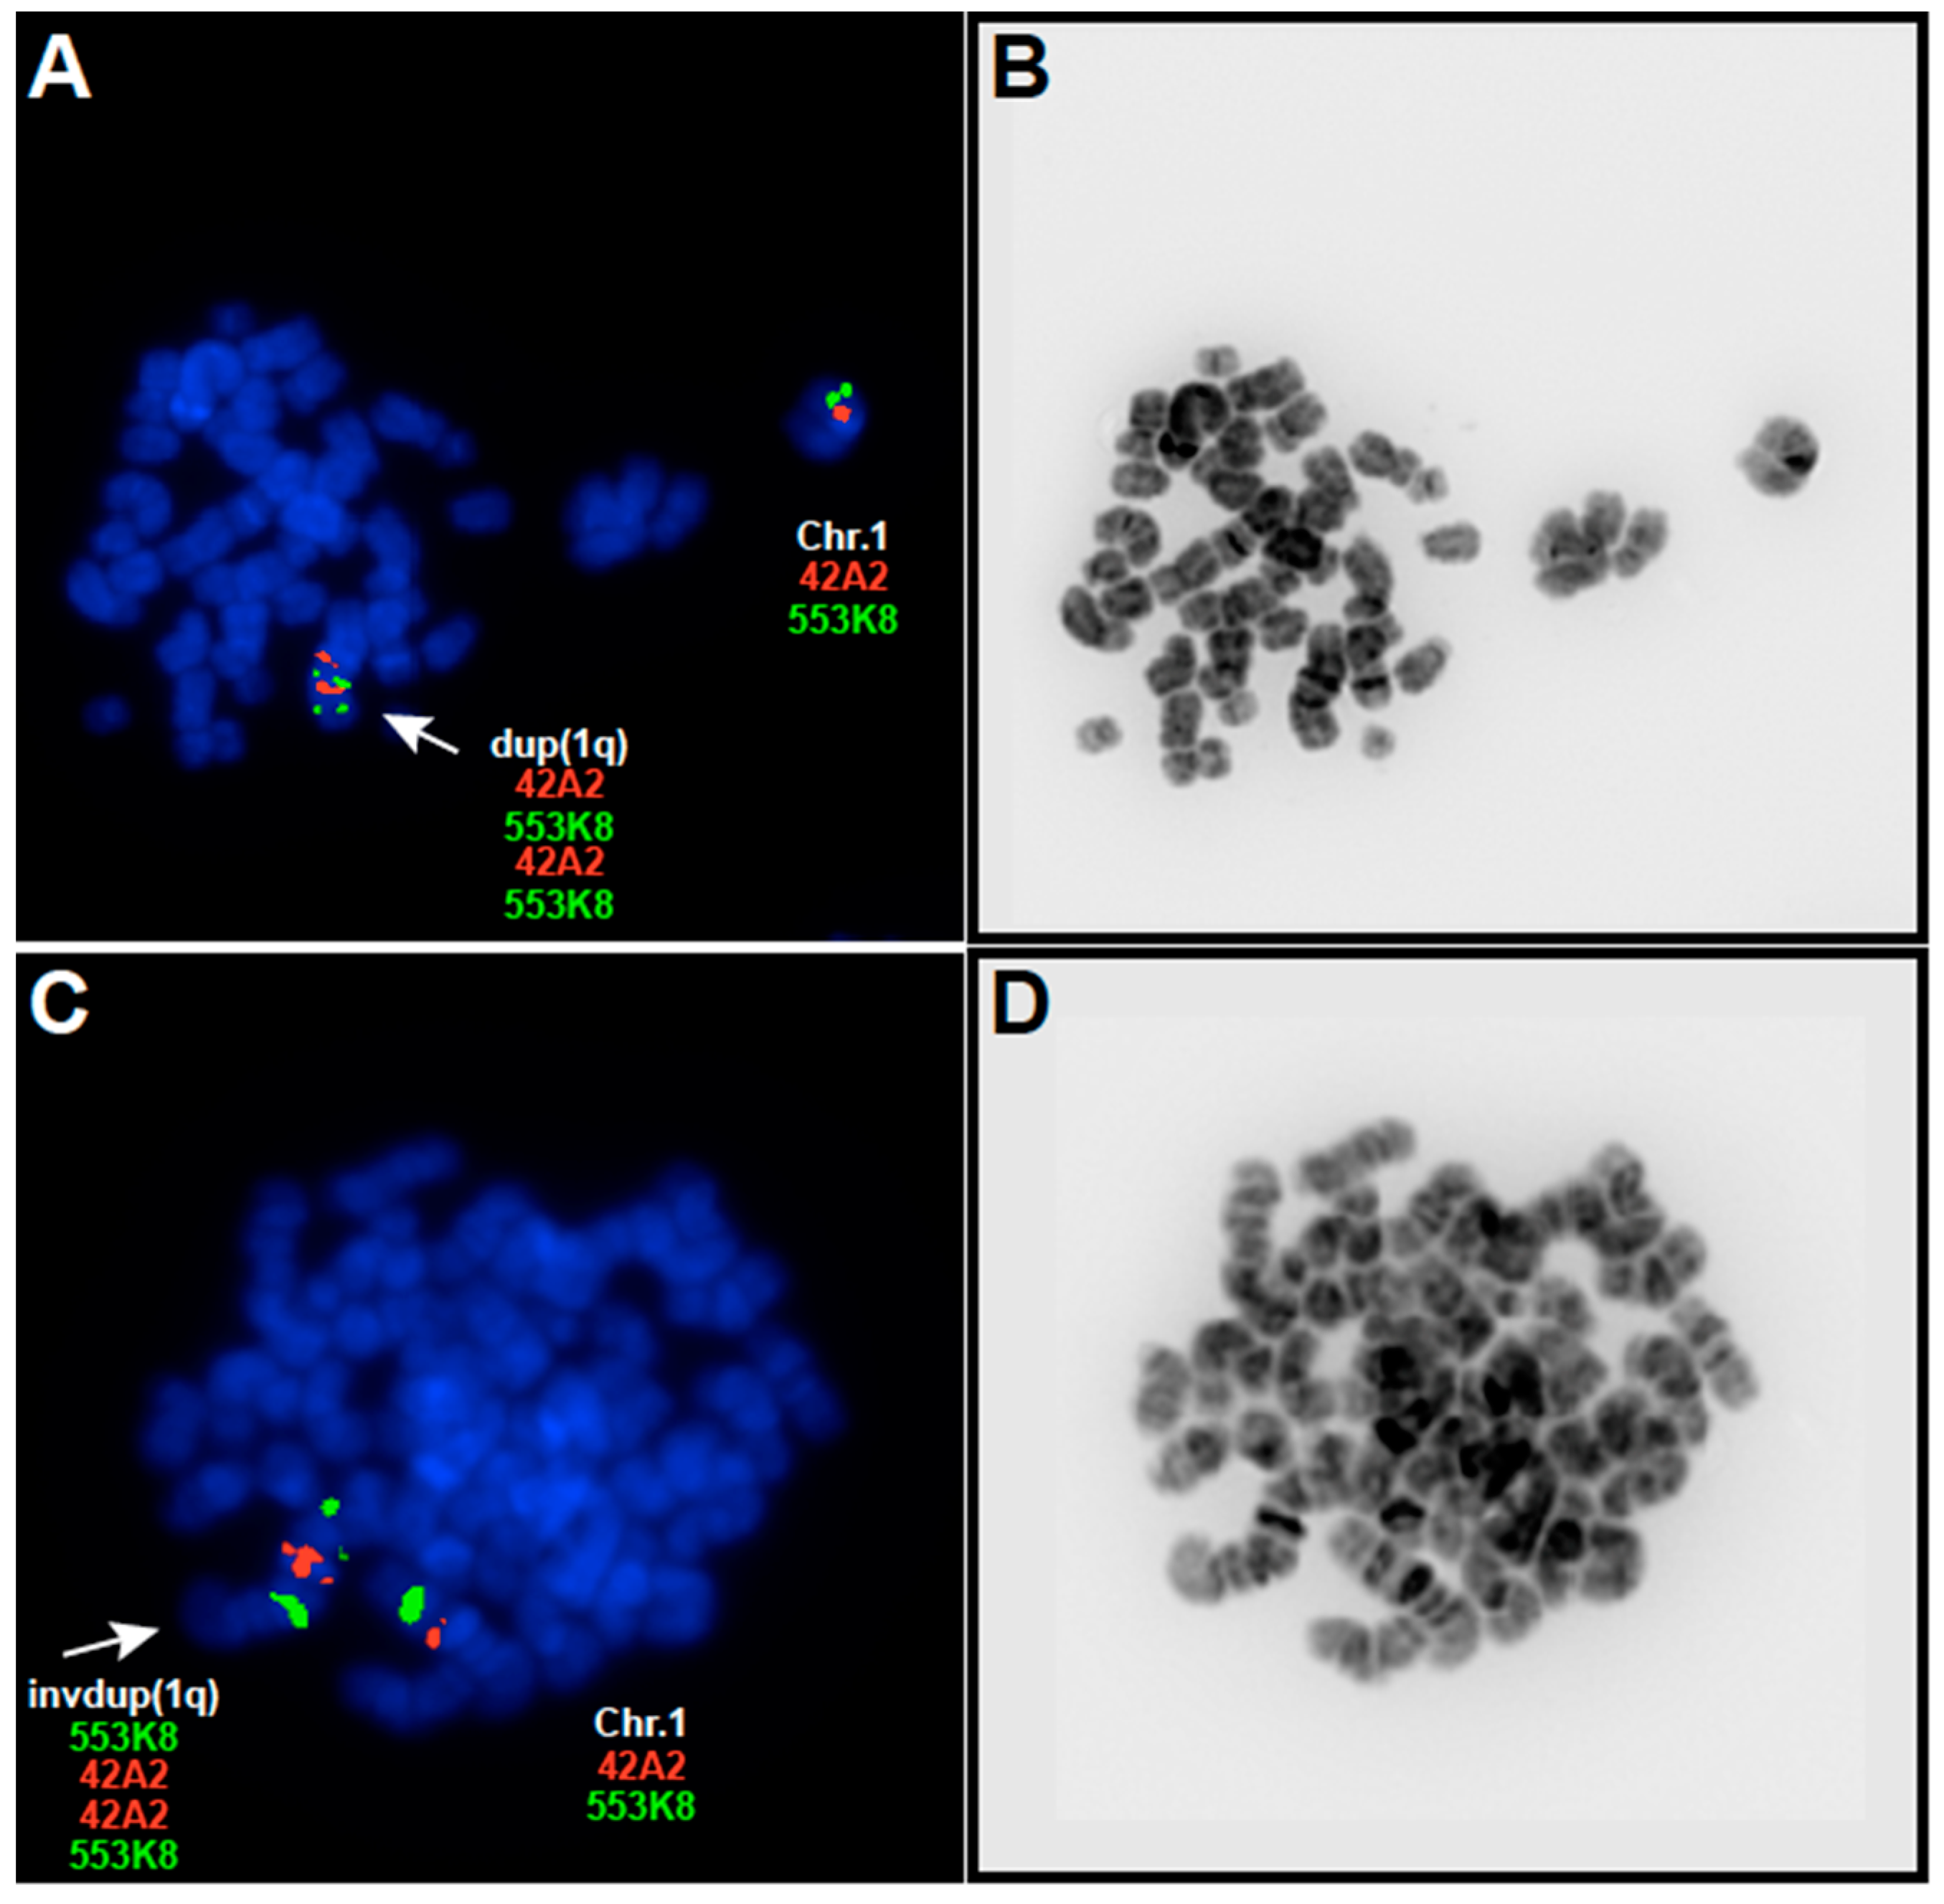

犬夜叉 スロット実機, EBV and 1q Gains Affect Gene and miRNA Expression in Burkitt,

EBV and 1q Gains Affect Gene and miRNA Expression in Burkitt, The DISC locus in psychiatric illness | Molecular Psychiatry,